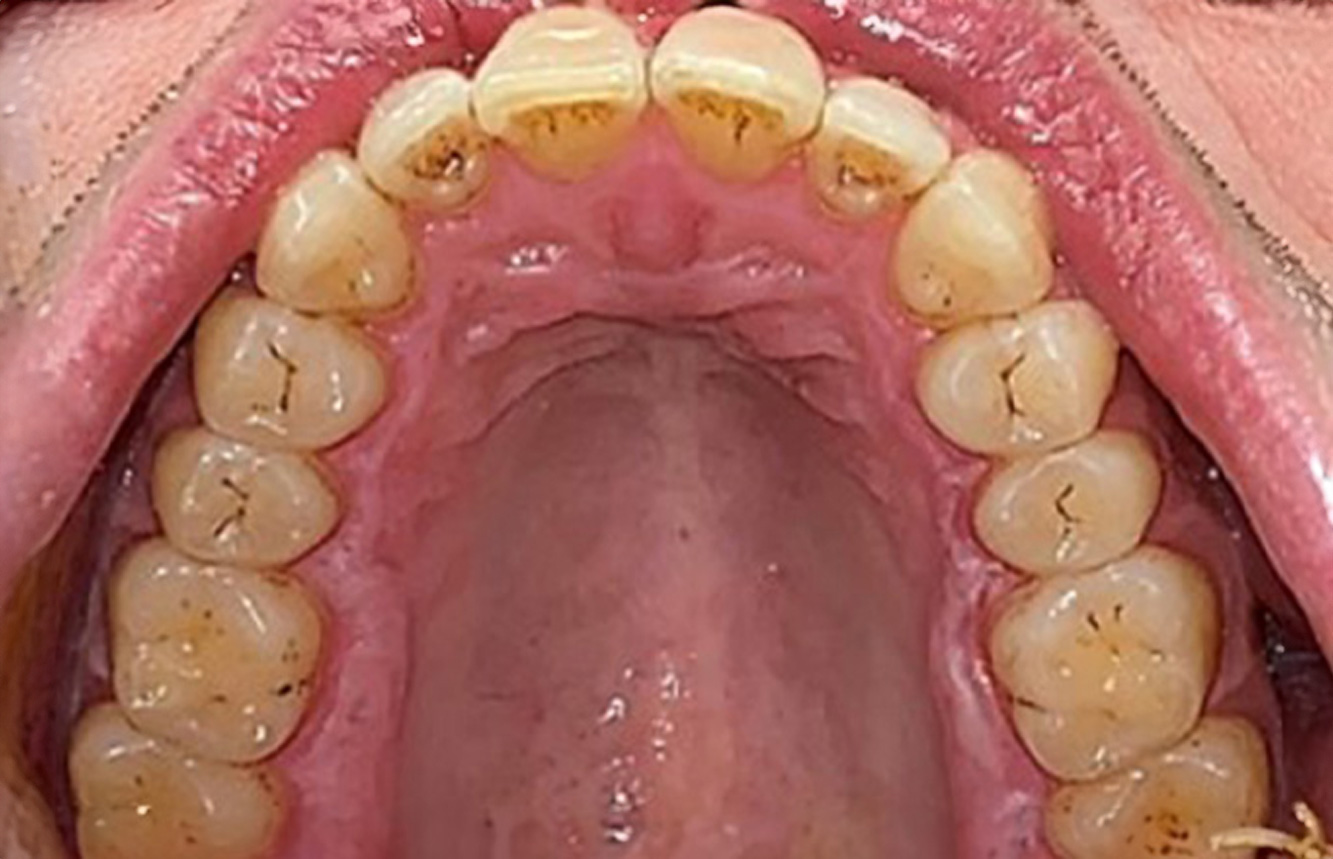

Patientenfälle nach IPC

Um das Zusammenspiel der für den IPC definierten Bedarfs- und Risikofaktoren sowie die Auswirkungen einzelner Faktoren zu illustrieren, dienen nachstehende Fallbeispiele*.

Fallpräsentation: Management komplexer Zahnprothetik

Es ist längst bekannt, dass Mundgesundheit und Allgemeingesundheit in direktem Zusammenhang stehen und einen zum Teil bidirektionalen Einfluss aufeinander haben. Die Berücksichtigung beider Faktoren sind bei der Planung der oralen Prävention und Therapie der Patienten in der Zahnarztpraxis unabdingbar. Dabei ist oberstes Ziel, die Gesundheit und die Lebensqualität der Patienten sowohl aus zahnmedizinischer -und medizinischer Sicht zu erhalten. mehr Infos